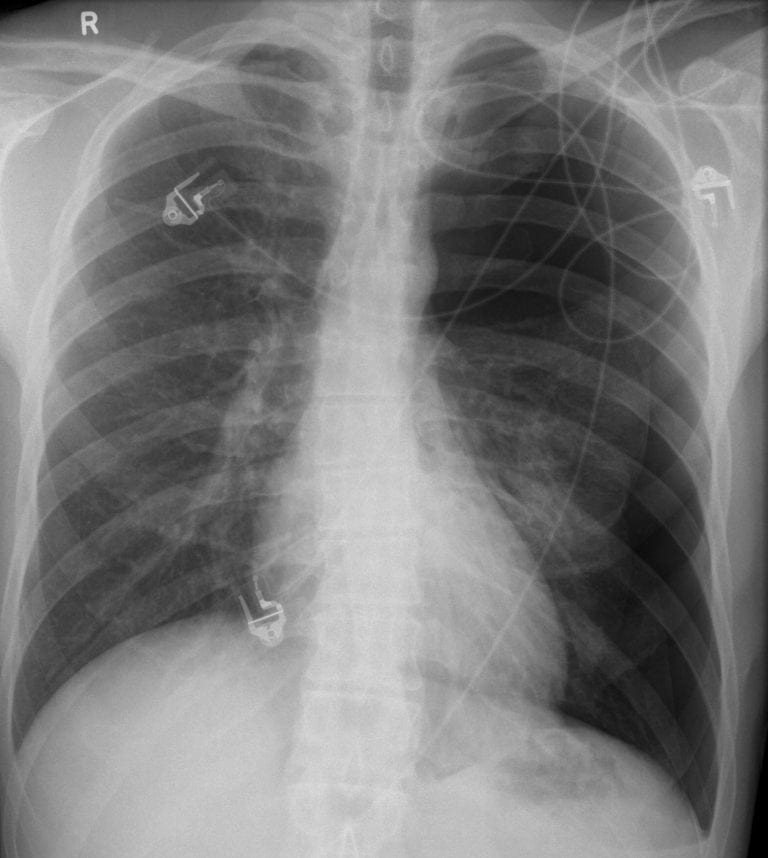

If you notice one or more of the signs below in yourself or someone else, call 911 or your local emergency number right away. Some of the causes of cardiac left side chest pain are narrowed arteries due to a buildup of plaque, angina, a shortage of blood supply to the heart (called myocardial ischemia), and a heart attack. Elefteriades explains, “chest pains or aches can be the result of coronary artery disease, valvular heart disease or aortic aneurysm.

Im experiencing pains in the left side of my chest and tingling in my left arm, i will inform you that two days ago i had an incident where i came inside after playing with my dogs and i became very dizzy and could taste a very pungent metallic or blood taste and have been to the er twice since then and have been turned away with no answers as to why i’m feeling this way. Is the chest pain constant or does it come and go? Symptoms could include new or unexplained chest pain coupled with shortness of breath, a cold sweat, nausea, fatigue or lightheadedness.

The pain extends to the jaw, left shoulder, and rarely to the back. Previously, it never lasted more than a day or two, and the intervals between events were substantial, but i've now had it for a week and a half straight. A sharp stabbing pain in the chest could be a sign of an injury, such as a strained chest muscle or a fractured rib bone.